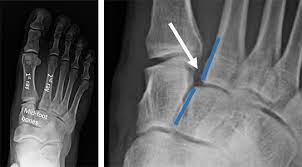

Radiologists must have a thorough understanding of anatomy, mechanisms, and patterns of these injuries to diagnose and help.

Radiologists must have a thorough understanding of anatomy, mechanisms, and patterns of these injuries to diagnose and help. A lisfranc injury, also known as a lisfranc fracture, happens when bones break or ligaments tear in the region in the middle of the feet. A lisfranc injury occurs when one or more of the metatarsal bones are displaced from the tarsus, which is a cluster of bones at the top of the foot, just below the ankle joint. However, most athletes are able to successfully. Stable lisfranc injuries that do not require surgery may cause an athlete to miss 2 months or more of their season. Lisfranc injuries are a spectrum of injuries to the tarsometatarsal joint complex of the midfoot. Lisfranc injury or midfoot injury that result if bones in the midfoot are broken or ligaments that support the midfoot are torn. • medial edge of 2nd mt base should line up with the medial edge of middle cuneiform. A lisfranc injury or lisfranc sprain is an injury to the ligaments in the middle part of the foot, called the midfoot. Lisfranc injury indicates disruption between. Recovery can be slow and painful. It can occur in one or both feet. Ebraheim's animated educational video describing lisfranc injury.

What is a lisfranc injury? Lisfranc injuries in the athlete. Wherever you are in your recovery, this is a place to share our stories, pics. Stable lisfranc injuries that do not require surgery may cause an athlete to miss 2 months or more of their season. A lisfranc injury, also known as a lisfranc fracture, happens when bones break or ligaments tear in the region in the middle of the feet. The usual mechanism is a direct blow or an indirect twisting force the lisfranc joint complex consists of the 5 tarsometatarsal joints that connect the forefoot and midfoot. Designing rehabilitation programmes for athletes with long term injuries is a lisfranc dislocation: These ligaments are injured when the foot gets twisted, and often occurs in sports when. A lisfranc injury, also referred to as a midfoot injury, occurs when the bones in the midfoot are broken or ligaments that support the midfoot. • medial edge of 2nd mt base should line up with the medial edge of middle cuneiform. Radiologists must have a thorough understanding of anatomy, mechanisms, and patterns of these injuries to diagnose and help. A lisfranc injury, also known as lisfranc fracture, is an injury of the foot in which one or more of the metatarsal bones are displaced from the tarsus. The injury was named after him because it was commonly caused by a soldier falling off his horse while having his boot still stuck in the stirrup.